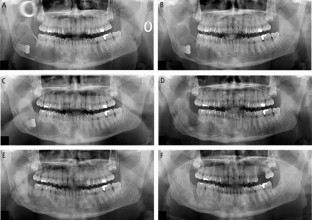

Jaw cysts are a common, yet diverse group of lesions often detected incidentally during routine dental examinations. While many cysts remain asymptomatic, larger, or aggressive, cysts can lead to significant complications, including tooth displacement, jaw fractures and nerve damage. This article reviews the pathophysiology, classification and management of jaw cysts, focusing on odontogenic cysts, which account for most cases presenting to oral and maxillofacial surgery. Various surgical techniques exist, including enucleation, marsupialisation, decompression, and en bloc resection, each with advantages, limitations, and indications based on cyst size, location, and recurrence risk. We present a case study illustrating a successful outcome using a two-staged treatment approach for a large dentigerous cyst. Selecting the appropriate management strategy requires careful consideration of lesion characteristics, patient factors, and recurrence risk, with the goal of minimising morbidity and optimising patient recovery and long-term outcomes.

Large jaw cysts can be effectively managed using a staged approach combining marsupialisation, decompression, and enucleation.

Minimally invasive techniques preserve anatomical structures and reduce morbidity while promoting gradual bone regeneration.

Careful case selection and long-term radiographic follow-up are essential to minimise recurrence risk and ensure successful outcomes.